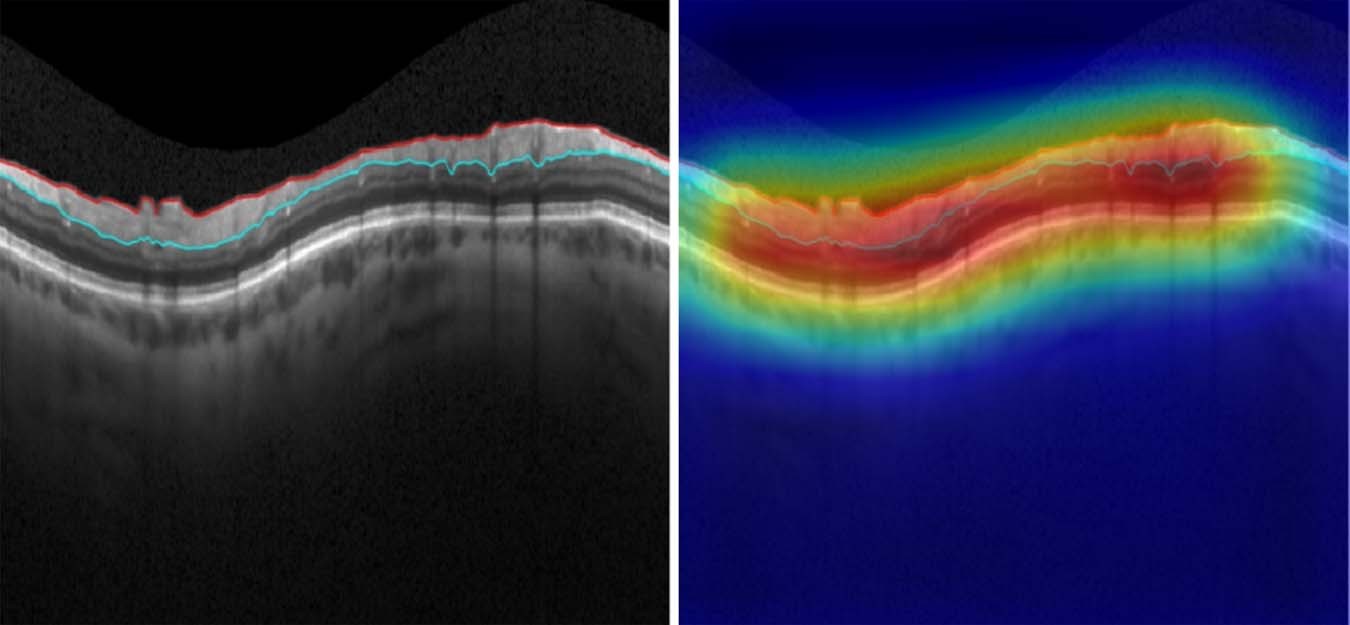

Figure 2

Spectral-domain optical coherence tomography (SDOCT) B-scan with no segmentation error, as labelled by human graders and the deep learning algorithm. Class activation map (heatmap) involves the whole B-scan, rather than being concentrated on a particular area. The probability of segmentation error given by the deep learning algorithm was below 1%.